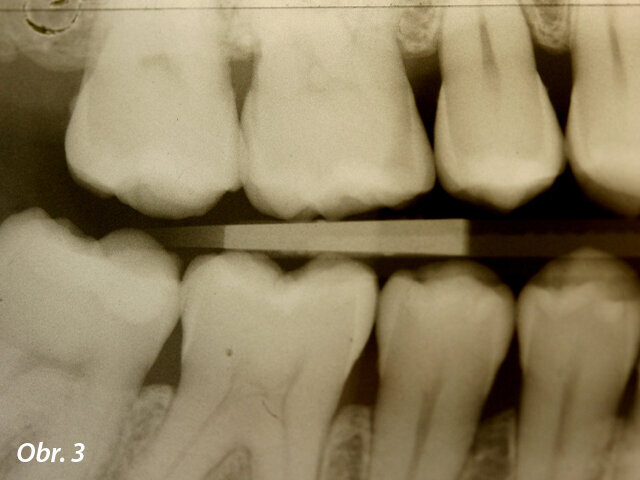

Kazuistika

Pacientka ve věku 38 let přišla do mé ordinace kvůli vyřešení zubních kazů. Při klinickém vyšetření nebyly patrné žádné kazy velkého rozsahu (obr. 1, 2). Až na RTG snímcích typu bitewing (obr. 3, 4), nezbytného prostředku pro diagnostiku v záchovné stomatologii, byly vidět mnohé kariézní léze, které zasahovaly do dentinových tkání. Pacientka požadovala vynikající estetický výsledek, což znamenalo sladění kompozitního materiálu se sklovinnými tkáněmi. Tento požadavek musel být zkombinován s funkční rehabilitací, která by v distálním úseku odolala zatížení žvýkacími silami a zajistila dlouhodobě minimální možné opotřebení. V rámci léčebného plánu bylo pacientce navrženo řešení v podobě přímého ošetření kazů v jednotlivých kvadrantech a nepřímé výplně v zubu 47, které by umožňovalo nejlepší přesnost okrajů a bylo zárukou dlouhodobě vynikajícího výsledku.